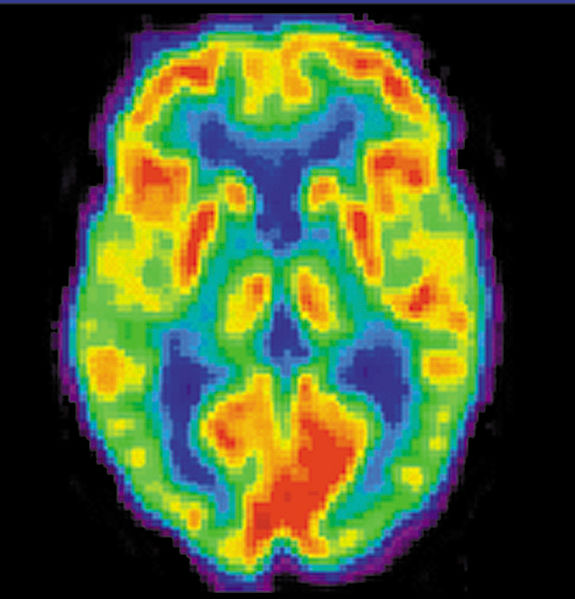

Interaxon, a Canadian based company, has been working on a number of neural interface gadgets. The gadgets rely on information obtained through a device placed in front of the user’s forehead, allowing the user to mentally manipulate whatever device you happen to be linked with at the time. So far, the technology can only read whether or not a person is focused or relaxed, as well as being able to determine basic emotions, but it isn’t able to read anyone’s mind, in the truest sense of the term. The concept behind this is basically to scan the brain for significant changes in the brain’s magnetic field. When different emotions come into play, different parts of the brain react in different ways. Since the brain works through tiny electrical impulses, the neural interface scanner is able to pick up the magnetic fields given off by groups of these impulses, and determine their frequencies. The system then responds to how high the concentration of a particular type of wave, in this case an alpha wave, is. CNN has a good video interview about it here: http://www.cnn.com/video/#/video/tech/2010/07/16/nr.gaming.with.mind.cnn, and you can access Interaxon’s website here: http://www.interaxon.ca/how_it_works